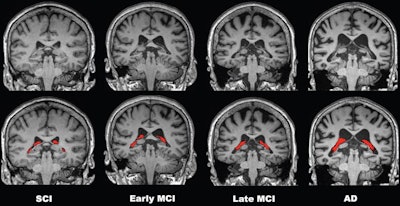

To elucidate this issue, the group analyzed imaging from a group of 532 patients with various stages of cognitive impairment due to Alzheimer's disease. Seventy-eight patients had subjective cognitive impairment (SCI), 158 had early mild cognitive impairment (MCI), 149 had late MCI, and 147 had Alzheimer's disease.

Results showed a stepwise increase in choroid plexus volume with severity of disease stage, with the SCI group having the smallest volumes and the Alzheimer's disease group having the largest. Moreover, the increase in choroid plexus volume was significantly associated with decreases in cortical and hippocampal volumes, which are more traditional markers of atrophy in Alzheimer's disease, according to the findings.